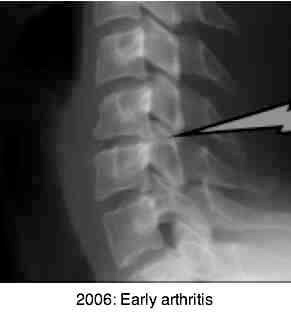

Notice the relatively minor degenerative changes in the first and third x-rays taken in 2006. The radiological report stated that there was slight loss of C5 on C6 disc space; the spinal canal had sufficient depth, and the foramina were all normal.

Notice the severe changes that have occurred in only three and a half years. I have only shown the right oblique, but the left is almost identical.

Notice the advanced degenerative changes in the unco-verebtral joints

bilaterally. The astonishingly swift development of Immobilisation Arthritis gives

testimony to the importance of normal joint nutrition and movement.